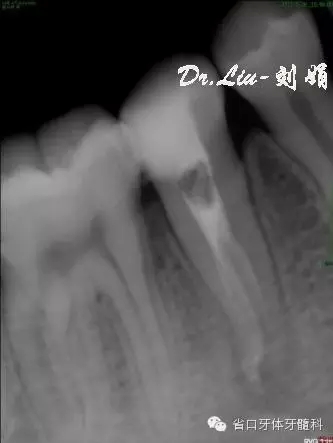

圖5:術(shù)中插尖片,見3根管

圖7:根備后封氫氧化鈣

圖8:1月后復(fù)診根尖低密度影有消退趨勢